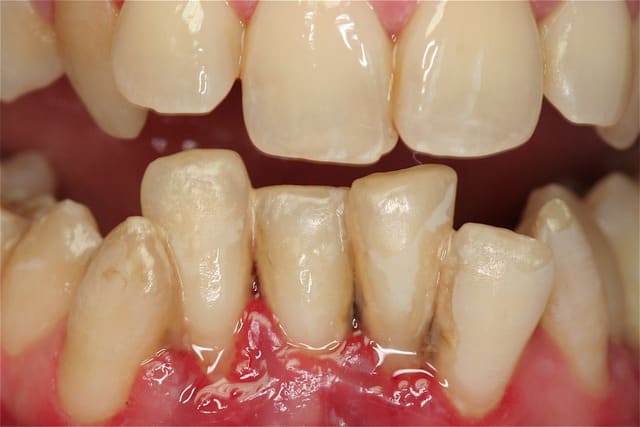

toujours aucune extractions depuis 8 ans, sur des cas de paro nommé irréparable par les plus grands parodontistes de France et de suisse! LOL

lus de 250 cas extrêmes et difficiles traités prouvent que nous sommes bien en présence d'une blessure souillée et qu'il suffit de la traiter comme toute blessure souillée.

donc ce qui me différencie de Jacques Charon et des aures , c'est que je ne parle plus en voyant le tableau clinique, saignements , gencive oedématiée, douleur, et gène fonctionnelle,(tous les signes d'une inflammation!), de "maladie" parodontale, mais bel et bien de "réparation" , cicatrisation, "voulue", dirigée et orchestrée, d'un point de vue biologique, car le corps n'a pas les moyens de se débarrasser des bactéries et autres corps étrangers, tartre notamment, installés sur la longueur de la racine, mais il a les moyens, et d'ailleurs l'article concernant l'inflammation, dans le numéro de Janvier de l'information dentaire, dossier "maladie parodontale" , le dit bien , que lors de l'inlammation, l'os est détruit! mais ce n'est pas une maladie, c'est un remède!

Les photos que tu montres ne donnent aucun renseignement quand à la guérison du parodonte (Ah oui , pardon ce n'est pas une maladie ).